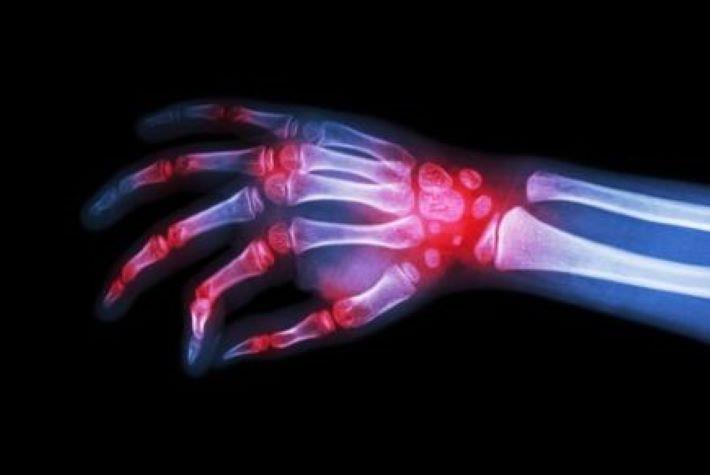

קסלג'אנז (טופסיטיניב) הוא תרופה ביולוגית שניתנת דרך הפה ומשמשת כקו טיפול שני לחולי דלקת מפרקים ראומטית. קסלג'אנז מעכבת אנזימי JAK kinase שמתווכים בתהליכי תגובה דלקתית, וכך מפחית בצורה משמעותית את הדלקת. כתוצאה, הטיפול בקסלג'אנז מתבטא בירידה בכאבי הפרקים ובנפיחות, שיפור המצב הכללי ועיכוב התקדמות המחלה. בנוסף, מיועד לטיפול בקוליטיס כיבית פעילה, בינונית עד חמורה למבוגרים מעל גיל 18, אשר טיפול מקובל (קונבנציונלי) או ביולוגי קודם לא היה יעיל, סביל או שהתגובה אליו אבדה.

צילום: shutterstock